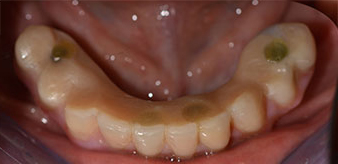

Successivamente, sono state prese le impronte e il morso di costruzione della paziente, per consentire al tecnico dentale di iniziare a realizzare la ricostruzione provvisoria. Quest'ultima è stata innestata lo stesso giorno (Fig. 17 e 18).

impianti

Fig. 17

Fig. 18